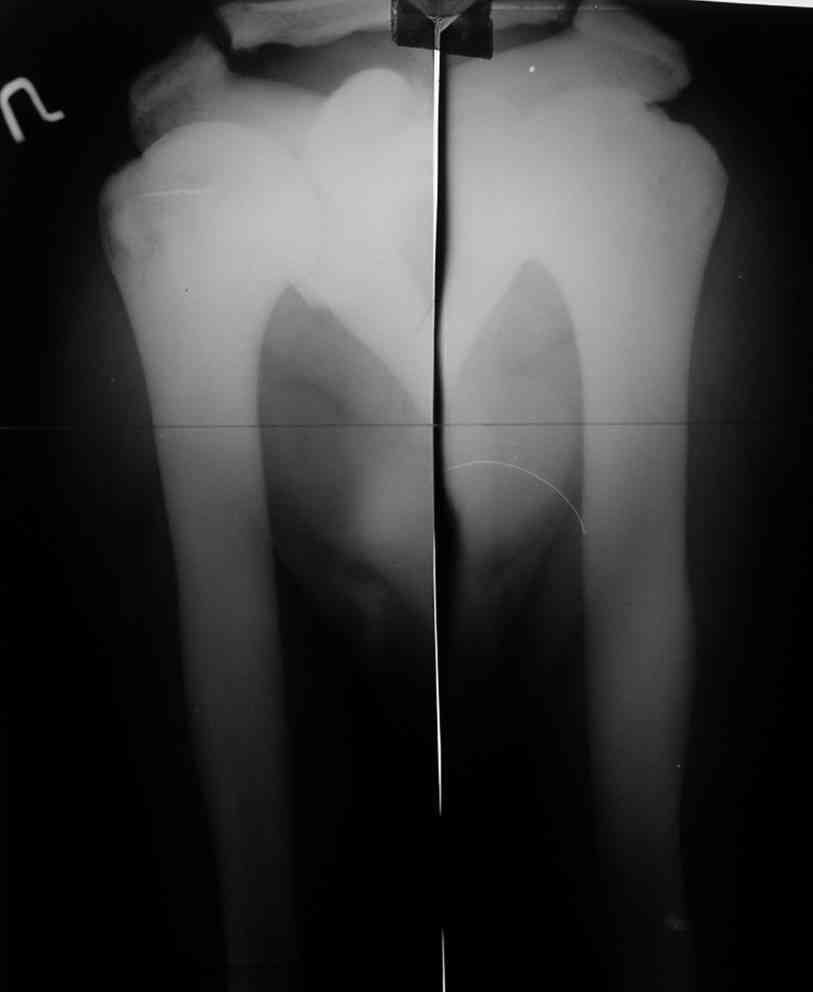

Представленные Вами данные о пациенте 57 дет с болезнью Альбертс-Шенберга чрезвычайно интересны, но диагноз вызывает большие сомнения. Для мраморной болезни характерно прееобладание склероза, а на представленных рентгенограммах преобладает симметричная дезорганизация архитектоники губчатой кости в эпиметафизарной зоне дистальных отделов бедер и голеней.

Мне кажется, представленные рентгенограммы скорее соответствуют варианту фиброзной дисплазии который был описан М. Campanacci (1976) или

Уважаемый Константин Иванович! Полностью согласен с проф. Михайловым, данный случай не похож на мраморную болезнь, при которой имеется резкое, строго симметричное и генерализованное уплотнение костной ткани (остеопетроз), и кость оказывается построенной преимущественно из гомогенного компактного костного вещества. Для примера привожу случай из архива нашего института (бедренные, плечевые кости и таз, рис 1,2,3)

Изменения структуры костей у Вашего пациента больше похожи на полиоссальную форму фиброзной дисплазии или болезнь Педжета, возможены также инфаркты костного мозга б.берцовых костей. К сожалению, качество снимка не очень хорошее, непонятно, сохранен ли кортикальный слой б.берцовых костей по передней поверхности.